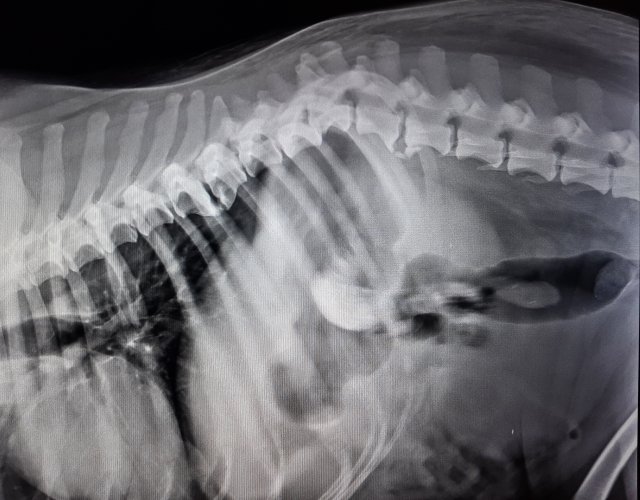

Acest câine a fost lovit de mașină și găsit pe marginea drumului, cu coloana fracturată în trei locuri. Nu a supraviețuit.